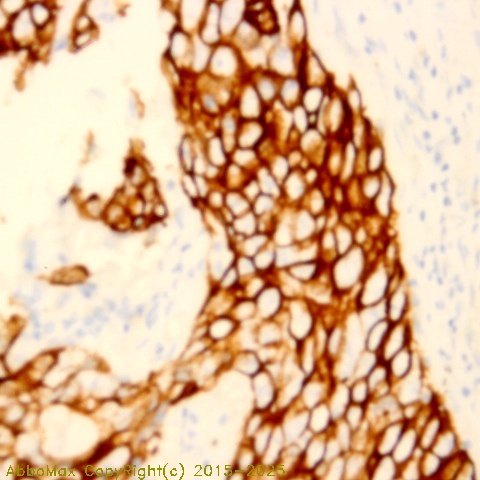

Cytokeratin 6

"Keratins are the intermediate filament proteins that form a dense meshwork of filaments throughout the cytoplasm of epithelial cells. The keratin proteins of epithelial tissues are commonly known as ""keratins"" or are sometimes referred to as ""cytokeratins"".The type II cytokeratins consist of basic or neutral proteins which are arranged in pairs of heterotypic keratin chains coexpressed during differentiation of simple and stratified epithelial tissues. As many as six of this type II cytokeratin (KRT6) have been identified; the multiplicity of the genes is attributed to successive gene duplication events. Keratin 6 is found mostly in squamous epithelium. Keratin 6A was the first type II keratin sequence determined. It is found with keratin 16 and/or keratin17 in the palm and sole epidermis, the epithelial cells of the nail bed, the tong, the epithelial lining of oral mucosa and esophagus, and hair follicles. This keratin 6 isoform is thought to be the most abundant of the K6 isoforms. Keratin 6B isoform is thought be less abundant than the closely related to keratin 6A protein. Keratin 6A gene silencing suppresses cell invasion and metastasis of nasopharyngeal carcinoma via the β catenin cascade"

This antibody recognizes human Cytokeratin 6 protein. The other species are not tested.

IHC

2-10 µg/ml